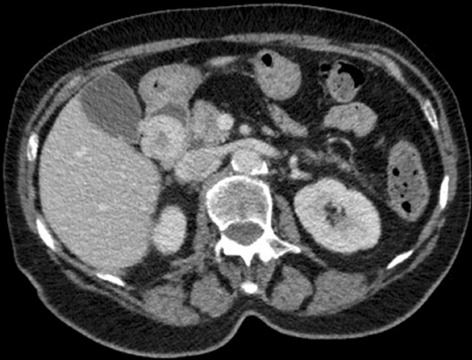

Result: The comparative analysis of the data shows a decrease in the number of presentations in ESU of AC cases during the pandemic, compared to the previous year, most often due to patients' fear of contacting the virus in the hospital environment. The median time between the onset of symptoms and the presentation in the ESU: 2020 – 14 days, 2019 – 5 days. Forms of moderate and severe AC predominated in the pandemic: GradeI—14.28%; GradeII—57.14%; GradeIII—28.57%. In 2019 GradeI—66.39%, GradeII—27.73%, GradeIII—5.88%. Laparoscopic cholecystectomy was attempted for all patients from the beginning, but the complications identified during surgery and severe forms led to a conversion rate in 2020 of 14.28%, compared to 5.88% in 2019. The severity of the cases is also observed in the postoperative complications encountered (perihepatic abscess Fig. 2. Figure 2, wound infection, bile leak; 2019—5.04%, 2020—23.21%), which required surgical reinterventions to solve them (2019: 2.52%, 2020: 10.71%). The number of deaths was significantly higher in 2020 (5.35%), compared to 2019 (0.84%).